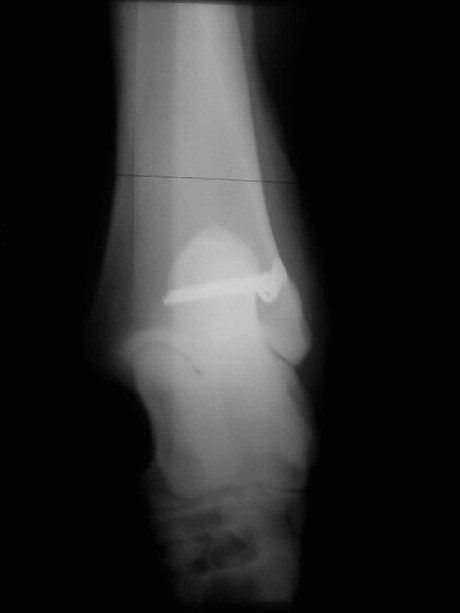

Erbsenbeinfraktur (Os accessorium)

Plattenverschraubung (cervikale Fusionsplatte aus Humanmedizin

zum Stabilisieren von Halswirbeln)